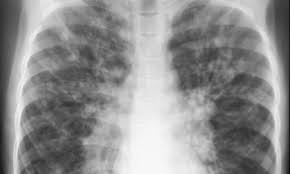

تليف الرئة

الرئتان هما عُضوا التنفُّس في الجهاز التنفسي، حيث يقعا بالقرب من العمود الفقري على جانبي القلب، وظيفتهما أخذ غاز الأكسجين من الجو، ثم تحويله داخل مجرى الدم، والتخلص من غاز ثاني أكسيد الكربون في مجرى الدم، وتسريحه في الهواء الخارجي، وذلك من خلال عملية التَنفُّس. تليف الرئة التليف هو عبارة عن تغيّر في توزيع الخلايا ووظائفها، ونمطها، حيث إنه يصيب العديد من الأعضاء، مثل القلب أو الرئتين، وعادة ما يحدث تليّف الرئة نتيجة سبب غير معروف، أو نتيجة الإصابة بالتهاب في الرئة، وخاصّةً في الأنسجة والحويصلات الهوائية، أو بالتهاب المفاصل المزمن، أو التهاب الذئبة الحمراء، أو تصلّب الجلد، أو السل، أو الاستنشاق المزمن لبعض المواد غير العضوية أو المواد العضوية، مثل السيليسكا، وغبار الحبوب، وفضلات الطيور، أو بعض الأدوية، كأدوية الأمراض المناعية، أو العلاج بالإشعاع، وغيره. عوامل زيادة خطر الإصابة بتليف الرئة التدخين. العامل الوراثي. طبيعة العمل، كالعمل في التعدين أو في مجال الزراعة. التقدم في السن. أعراض تليف الرئة النقص الحاد في مستوى الأكسجين في الدم. زيادة مستوى الهيموغلوبين في الدم. زيادة الشعور بالتعب والإرهاق. السعال الجاف. الشعور بعدم الارتياح في الصدر. انخفاض في الوزن. الألم في العضلات والمفاصل. مضاعفات تليف الرئة سرطان الرئة. فشل رئوي. زيادة الضغط الشرياني الرئوي. فشل قلبي. تشخيص تليف الرئة لتشخيص الإصابة تتم الاستعانة بالأدوات والفحوص الآتية: إجراء فحوصات الدم. فحوصات خاصة بالتهاب المفاصل. فحص وظائف الرئة، وتقييم قدرتها على نقل الأكسجين للدم. قياس حجم الرئة. قياس نسبة الأكسجين في الدم. عمل اختبارات الجهد. صورة أشعة مقطعية للصدر. أخذ عينة من الرئة عن طريق عملية المنظار التي تتم تحت تخدير موضعي. الأشعة السينية X-RAY. الموجات الصوتية للقلب. منظار للقصبات. ممارسة اختبار التحمل. علاج تليف الرئة والوقاية منه بالأدوية، عن طريق تقديم مشتقات الكورتيزون لعدة أشهر، ثم يتم تغيرها في حال عدم الاستجابة. معالجة السبب الأساسي الذي أدى للمرض.